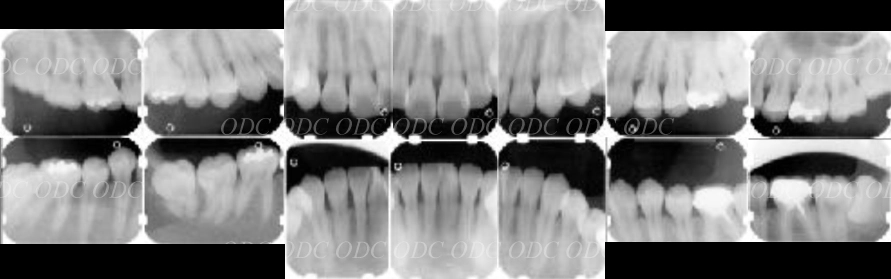

術前 2006年。

インプラント埋入予定部位のCT断面。

術後 2024年。

インプラント埋入及びチタンメッシュを使用した骨造成部位のCT断面。

インプラント治療が長期で安定するために、インプラント体の周囲の環境を整えることも大切です。

インプラント体が長期で安定するために、インプラントの周囲には十分な骨が存在する必要があります。

上段の写真は、高さが不足している場合の骨造成の写真です。

チタンメッシュ(チタン網)と人工骨を使用して埋入前に十分な骨を造成いたします。

インプラント体の周囲に十分な量の骨量と十分な量のしっかりとした歯ぐきを付与することは、インプラント治療が長期で安定するためにとても重要な要素となります。